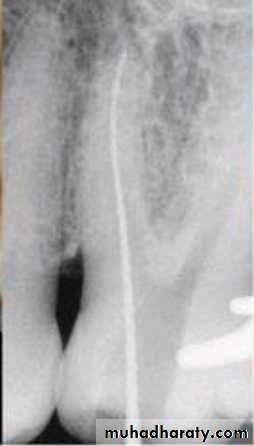

Standardized Technique

Standardized tech. Illustration